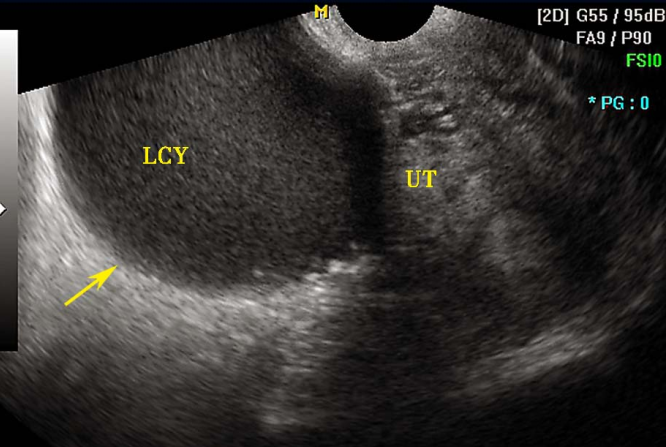

1.影像学检查 超声检查是诊断卵巢异位囊肿和膀胱、直肠内异症的重要方法,可确定异位囊肿位置、大小和形状,其诊断敏感性和特异性均在96%以上。囊肿呈圆形或椭圆形,与周围特别与子宫粘连,囊壁厚而粗糙,囊内有细小的絮状光点。因囊肿回声图像无特异性,不能单纯依靠B型超声图像确诊。盆腔CT及MRI对盆腔内异症有诊断价值,但费用昂贵,不作为初选的诊断方法。

卵巢子宫内膜异位囊肿B超